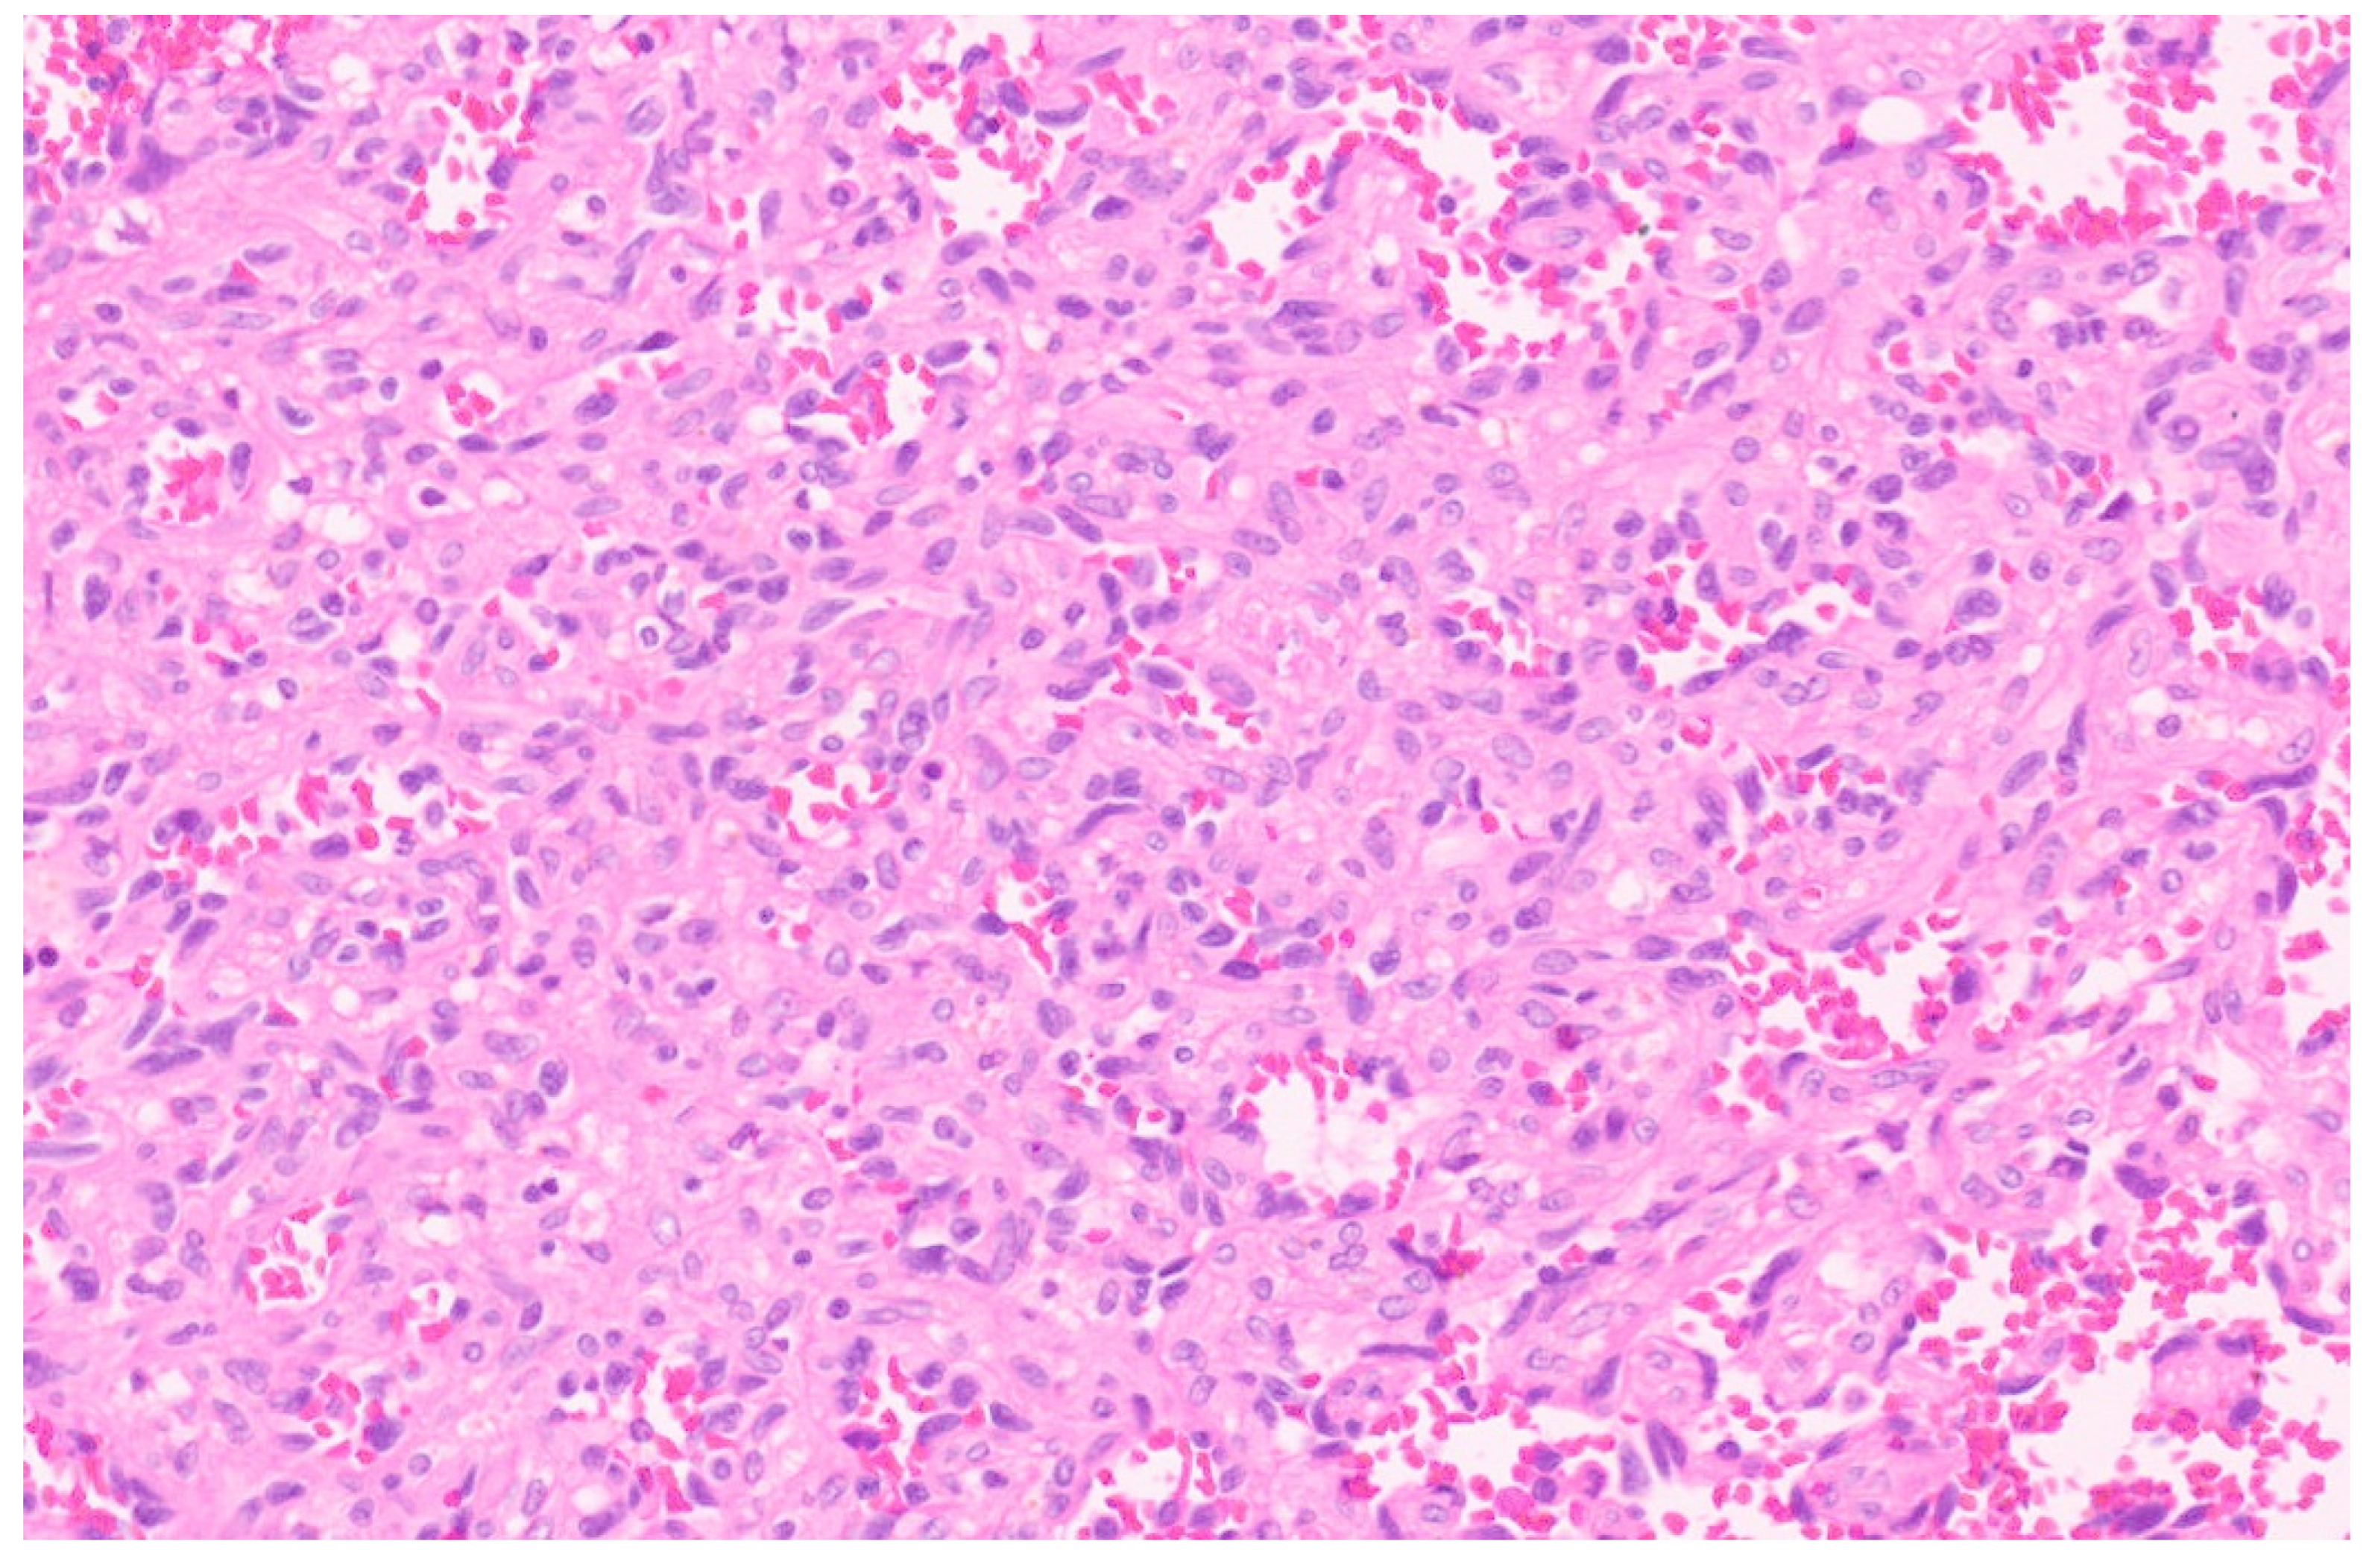

10.3. Pathology